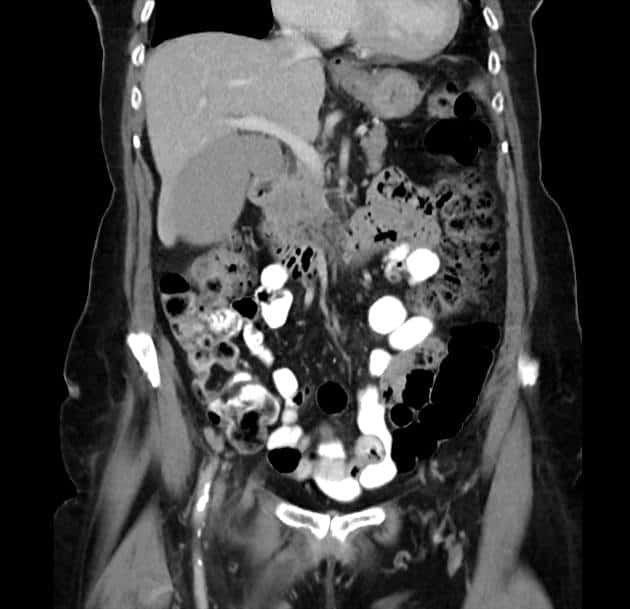

Thoát vị De Garengeot

» Thông tin: Nữ giới – 85 tuổi.

» Lâm sàng: Đau háng phải.